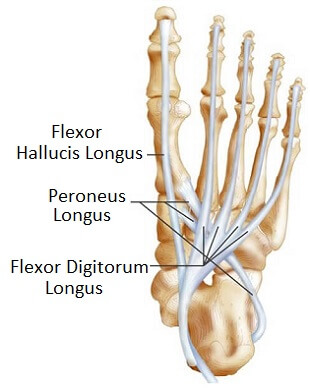

Foot Ankle Tendons Anatomy Function Injuries